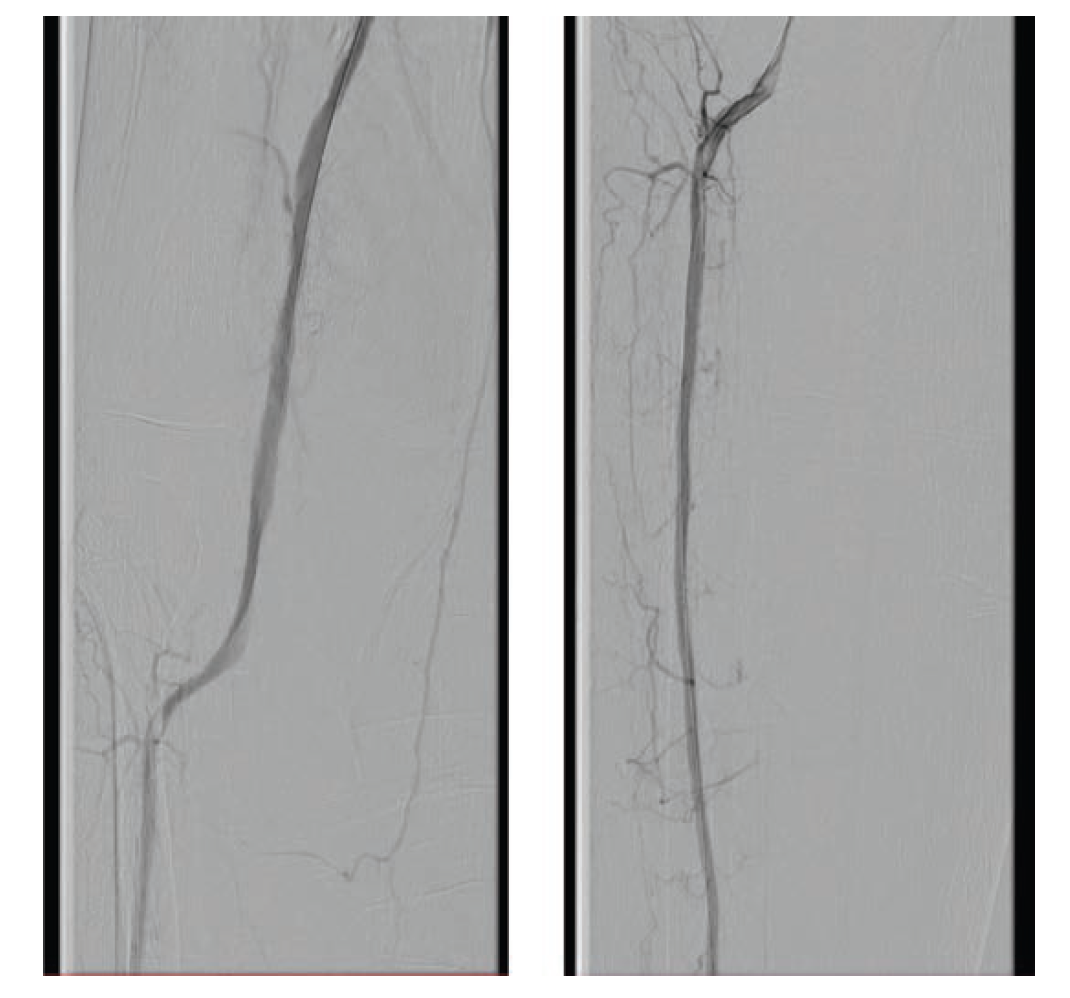

A 70-year-old man was referred for consideration of right lower extremity (RLE) intervention after initially presenting with resting ischemic pain and early tissue necrosis of the metatarsals, consistent with critical RLE ischemia. The patient was taken to the catheterization lab, where contralateral left common femoral artery (CFA) access was gained using a Micropuncture needle (Cook Medical) under ultrasound guidance. A 6F, 11 cm arterial sheath was placed into the artery over a guidewire. The right common iliac artery was engaged using a 5F internal mammary artery catheter; a 0.035" stiff-angled Glidewire (Terumo Interventional Systems) was then advanced to the right CFA. Peripheral angiography of the RLE was performed, demonstrating a total occlusion of the superficial femoral artery (SFA) as well as total occlusion of the popliteal artery and all three infrapopliteal vessels (Figure 1 and Figure 2). The 6F sheath was then exchanged over the Glidewire for a 6F, 45 cm sheath. At this time, anticoagulation was initiated with intravenous unfractionated heparin at 80 units/kg to achieve an activated clotting time (ACT) > 250 seconds.